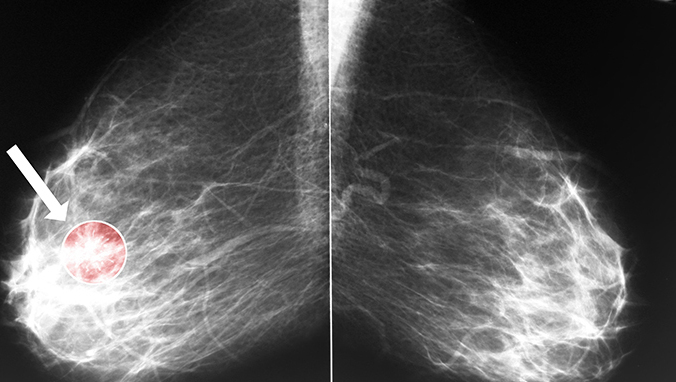

Breast cancer metastases how long the liver can live

Breast glands support and fix the breast. The glandular epidermis of the breast is produced by malignant cancer cells, especially those families with a history of breast cancer, old age, la